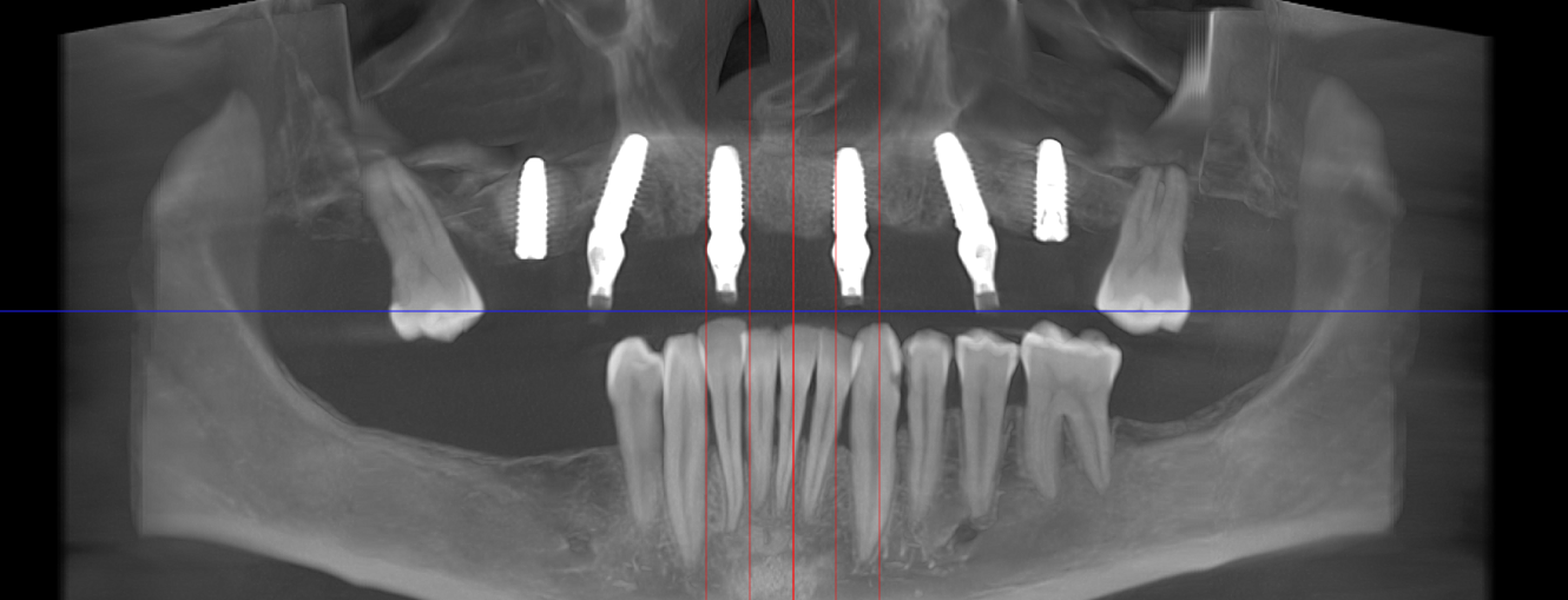

Metoda All-on-6 presupune inserarea chirurgicală a șase implanturi plasate strategic, pentru a asigura o proteză fixă stabilă și durabilă. Spre deosebire de conceptul All-on-4, recomandat în special pacienților cu deficit osos în zonele laterale ale maxilarului, All-on-6 are indicații mai largi și poate fi utilizat la majoritatea categoriilor de pacienți.

Caz 2

- Șase implanturi;

- Șase multiunit-uri, drepte sau angulate, în funcție de necesitățile protetice;

- Investigație imagistică completă, ideal CBCT (computer tomografie);